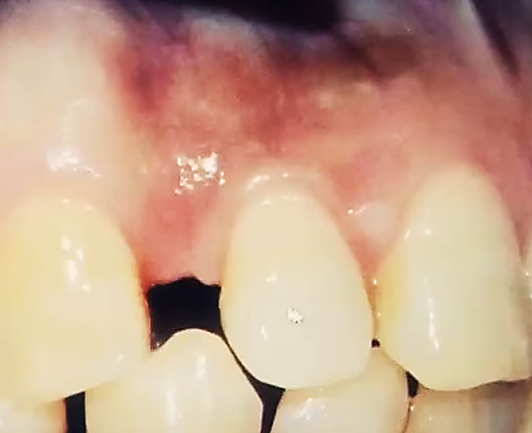

-치아를 턱뼈에 붙여주는 기능이 저하되어 치주염이 생긴다.